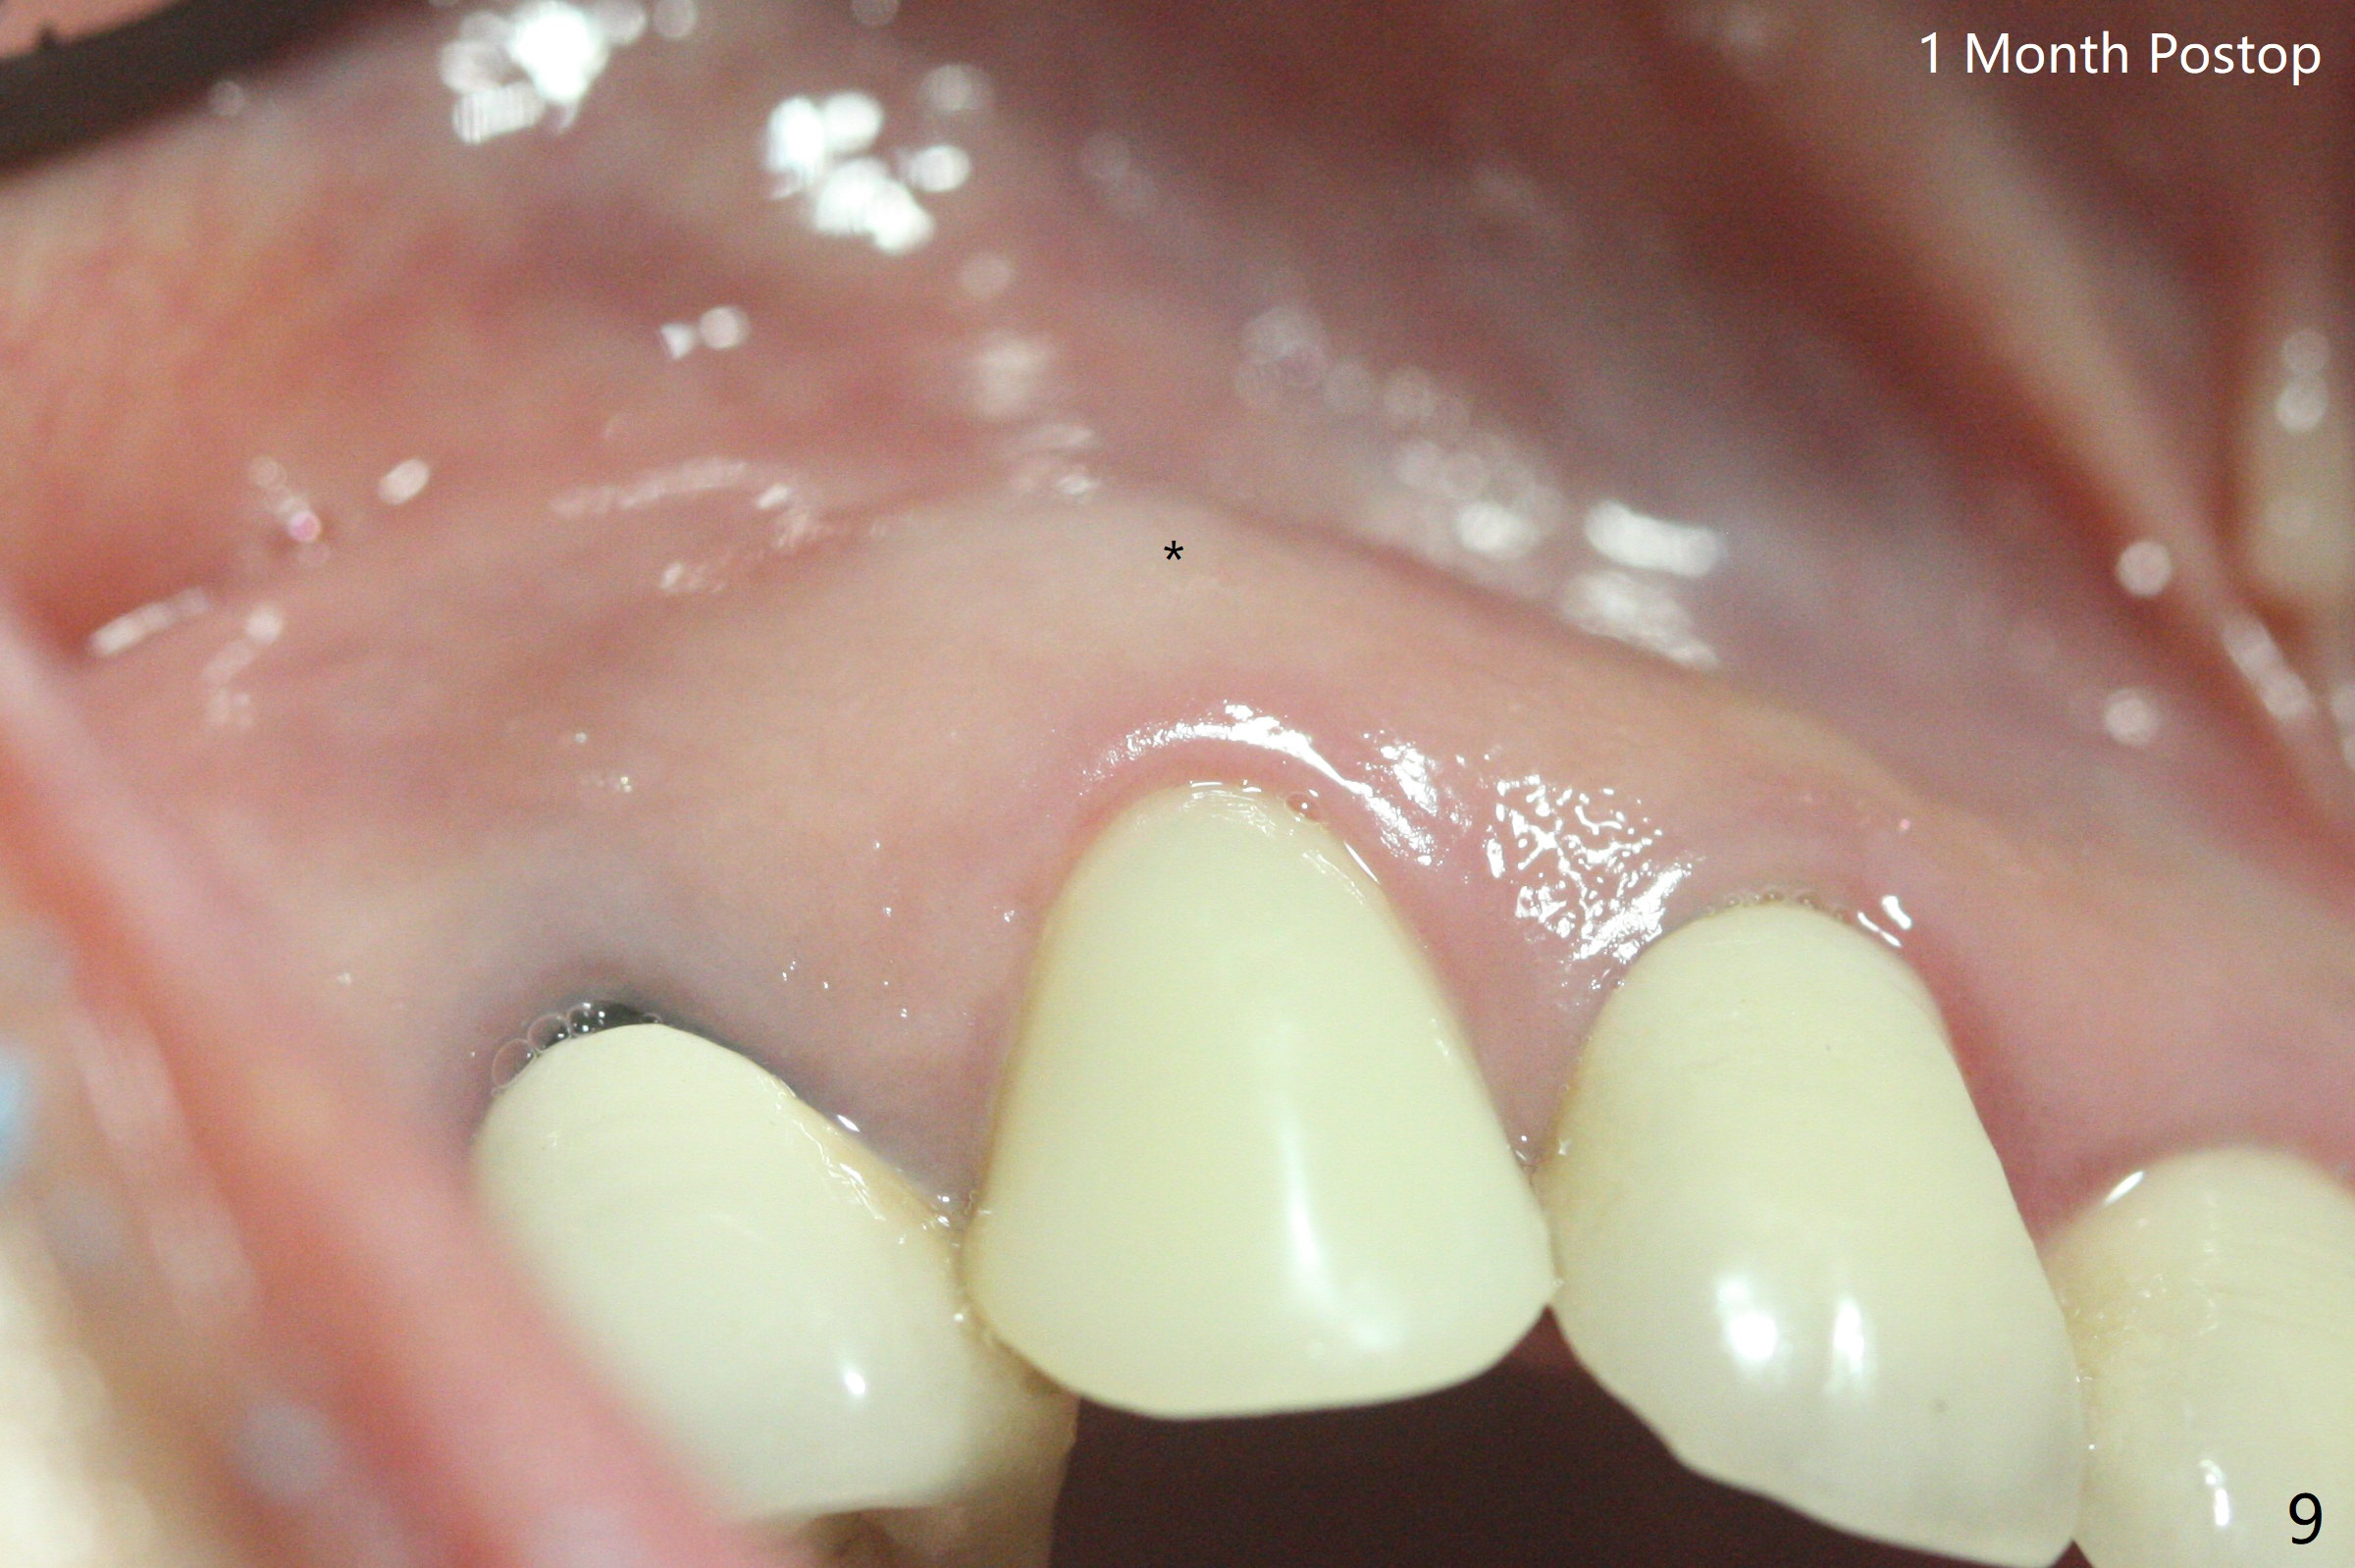

防止拔牙后颊侧骨板萎缩最有效方法是保留部分牙根,例如颊侧(外形象盾牌,简称盾,socket shield (S)),但是制备特别麻烦,尤其是上尖牙。60岁女右上3颊侧骨板隆起(图一至三:*),但是相当狭窄(上下方向),预计强行拔除,势必损失颊侧骨板,造成颊侧塌陷,准备保留盾,如图三红虚线,图六(术后3D长轴断面(十字架:植体))S代表。其实术中试图将整个牙根一起拔除,但是仿佛不行,只好静下心来分根,制备盾,不过困难重重,尤其是除去根尖(防止残余感染),最长外科裂钻似乎达不到根尖,取出后者,颊侧根尖骨板穿孔(图七:箭头)。然后腭侧钻洞(图四),当最后一个钻头保持原位时,在颊侧根尖穿孔处植入粘性骨粉(从牙槽窝口进入,原本粘性骨粉为了修复大面积颊侧缺损用(万一需要强行拔除)),然后才把一段式植体植入(图五),在其余空间填入骨粉,稍微制备基台,制作临时牙冠,最后在牙槽窝开口塞入PRF膜,衬里牙冠,不暂时取出牙冠,衬里相当于临时粘固剂。术后一个月牙根片段和临时牙冠维持良好的牙龈外形(图八,九);术后两个月病人嫌尖牙龈端太尖太长,临时牙冠龈端调整(图十,十一),但愿一个月后龈缘合乎病人期望。